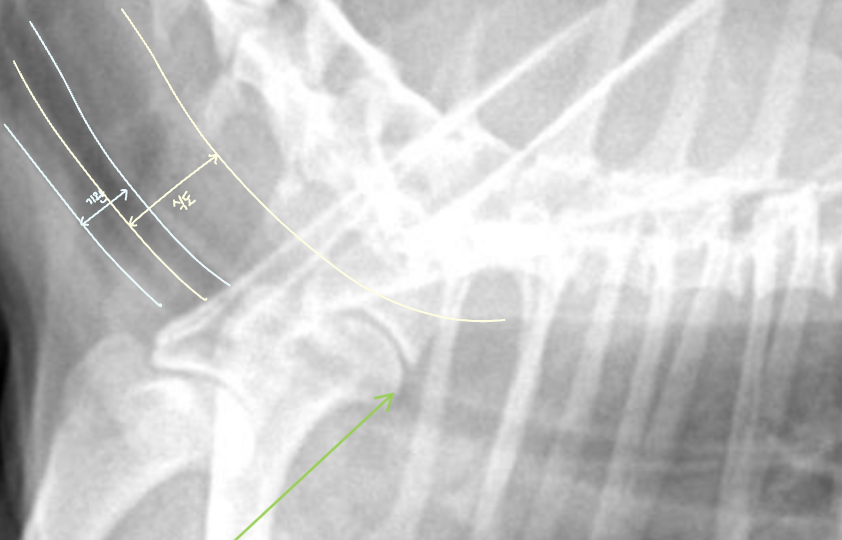

Tracheoesophageal strip sign (์๋ ๋ด ๊ฐ์ค ์ถ์ )

- Tracheoesophageal strip sign : ์๋ ํ์ฅ์ ์ํด ๊ธฐ๊ด๊ณผ ์๋๊ฐ ๊ฒน์ณ ๋ํ๋๋ ๊ฐ๋๊ณ ํํํ ๊ณต๊ธฐ ์์.

- ์๋์ ๊ฐ์ค ์ถ์ ๋์ด ์๋ค๋ฉด

- ํฅ๋ถ์ด๋ ๋ง์ทจ๋ก ์ธํ ์ผ์์ ์ถ์ (์ ์)

- ์ด๋ฌผ๋ก ์ธํ ๋งํ

- MG์ ์ํ ์๋ํ์ฅ์ฆ (์๋๊ทผ ๋ฌด๋ ฅํ)

| ์ ์ | Strip sign |